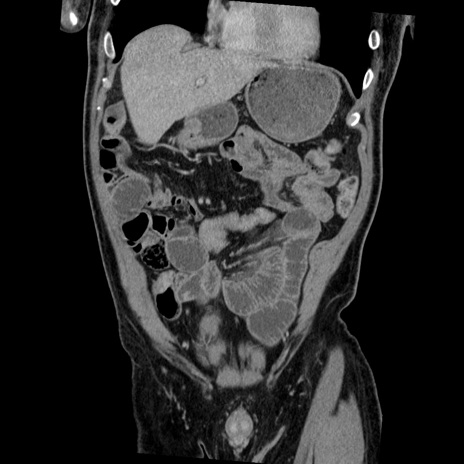

症例22(冠状断像)

【症例】50歳代男性

【主訴】腹痛

【現病歴】AVMからの被殻出血のため回復期リハ病棟入院中。 本日午後3時頃急に下腹部痛が出現した。

【既往歴】AVM、被殻出血、虫垂炎、高血圧

【身体所見】意識晴明、左半身不全麻痺、会話の理解は良好、36.5°C、腹部:膨隆、全体に板状硬、下腹部正中に圧痛点あり、反跳痛-、筋性防御不明、右下腹部にope scar

【データ】WBC 9400、CRP 0.06

横断像